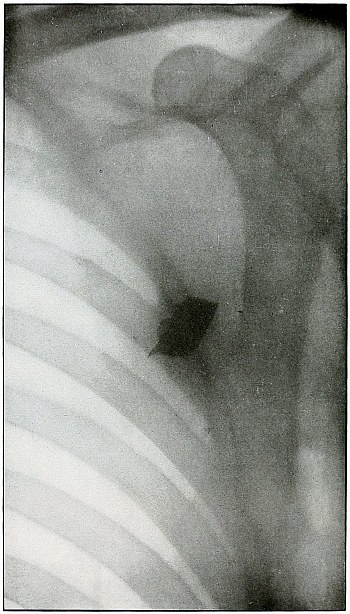

| 82.[Pg 5] |

Gunshot wound, shoulder |

174 |

| 83. |

Gunshot wound, shoulder |

176 |

| 84. |

Gunshot wound, shoulder |

178 |

| 85. |

Gunshot wound, shoulder |

180 |